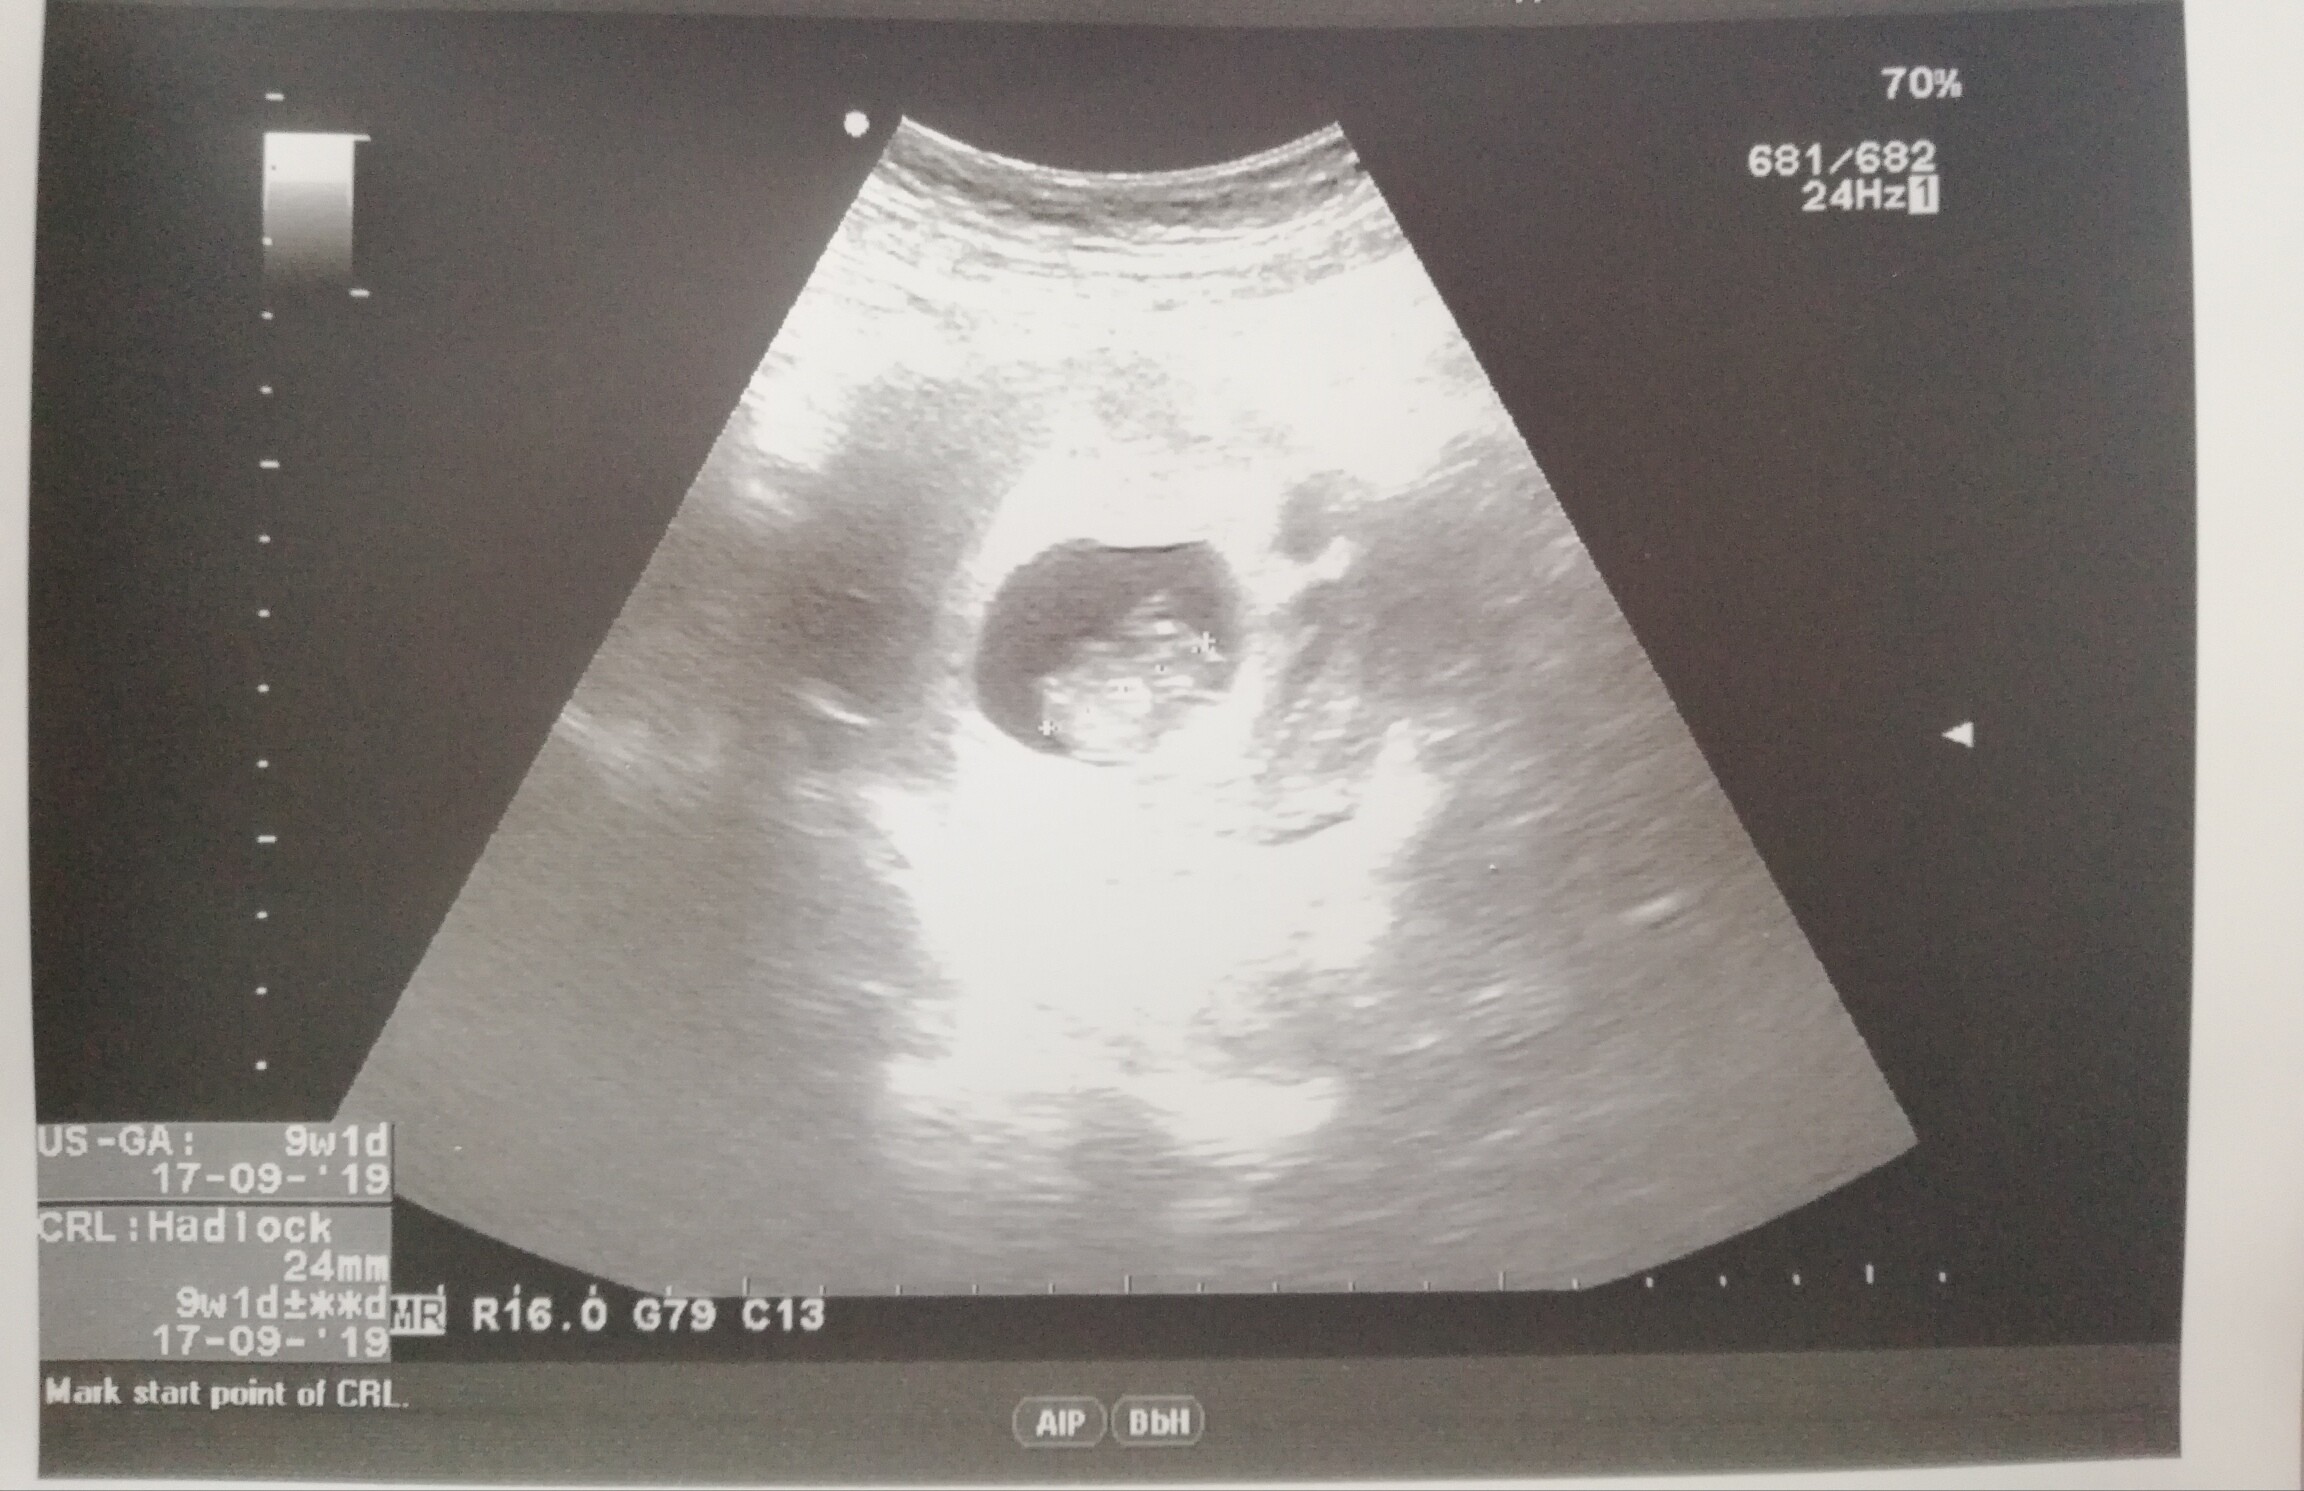

Kochane jeszcze ja dzisiaj miałam wizytę :D badania wszystkie ok, z fasolką też wszystko w porządku, ma całe 2,4cm :D następna wizyta dopiero za miesiąc-13.03, a 07.03 prenatalne :) współczuję wam tych mdłości i wymiotów, u mnie prawie zero objawów, w ogóle nie czuje się jakbym była w ciąży. Tylko bolą mnie wieczorami piersi, czuję się trochę zmęczona i strasznie bolą mnie plecy w części lędźwiowej :(

IMG_20190213_204333.jpg